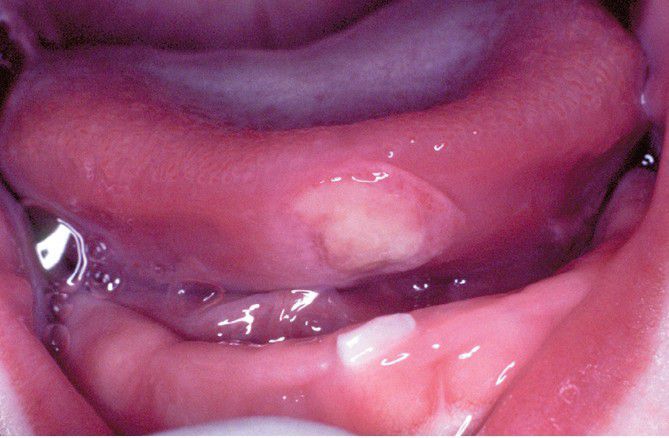

Riga-Fede Disease.

Newborn with traumatic ulceration of anterior ventral surface of the tongue. Mucosal damage occurred from contact of tongue with adjacent tooth during breastfeeding.